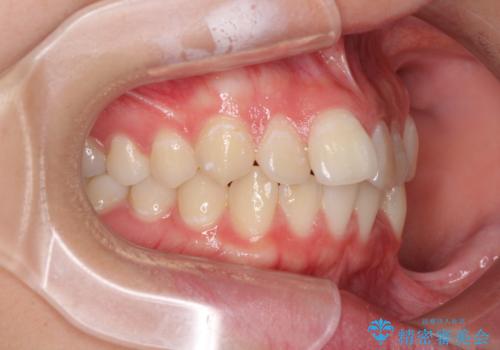

前歯のデコボコを改善 インビザライン矯正

- 口元のデコボコを気にして来院された患者様です。

前歯の捻れにより口元が閉じにくくなっていたため、歯列全体の側方への拡大と、歯と歯の間を少し削ってスペースを獲得することとしました。

ゴムかけをしっかりと行ってもらい、スッキリとした口元に仕上げることができました。